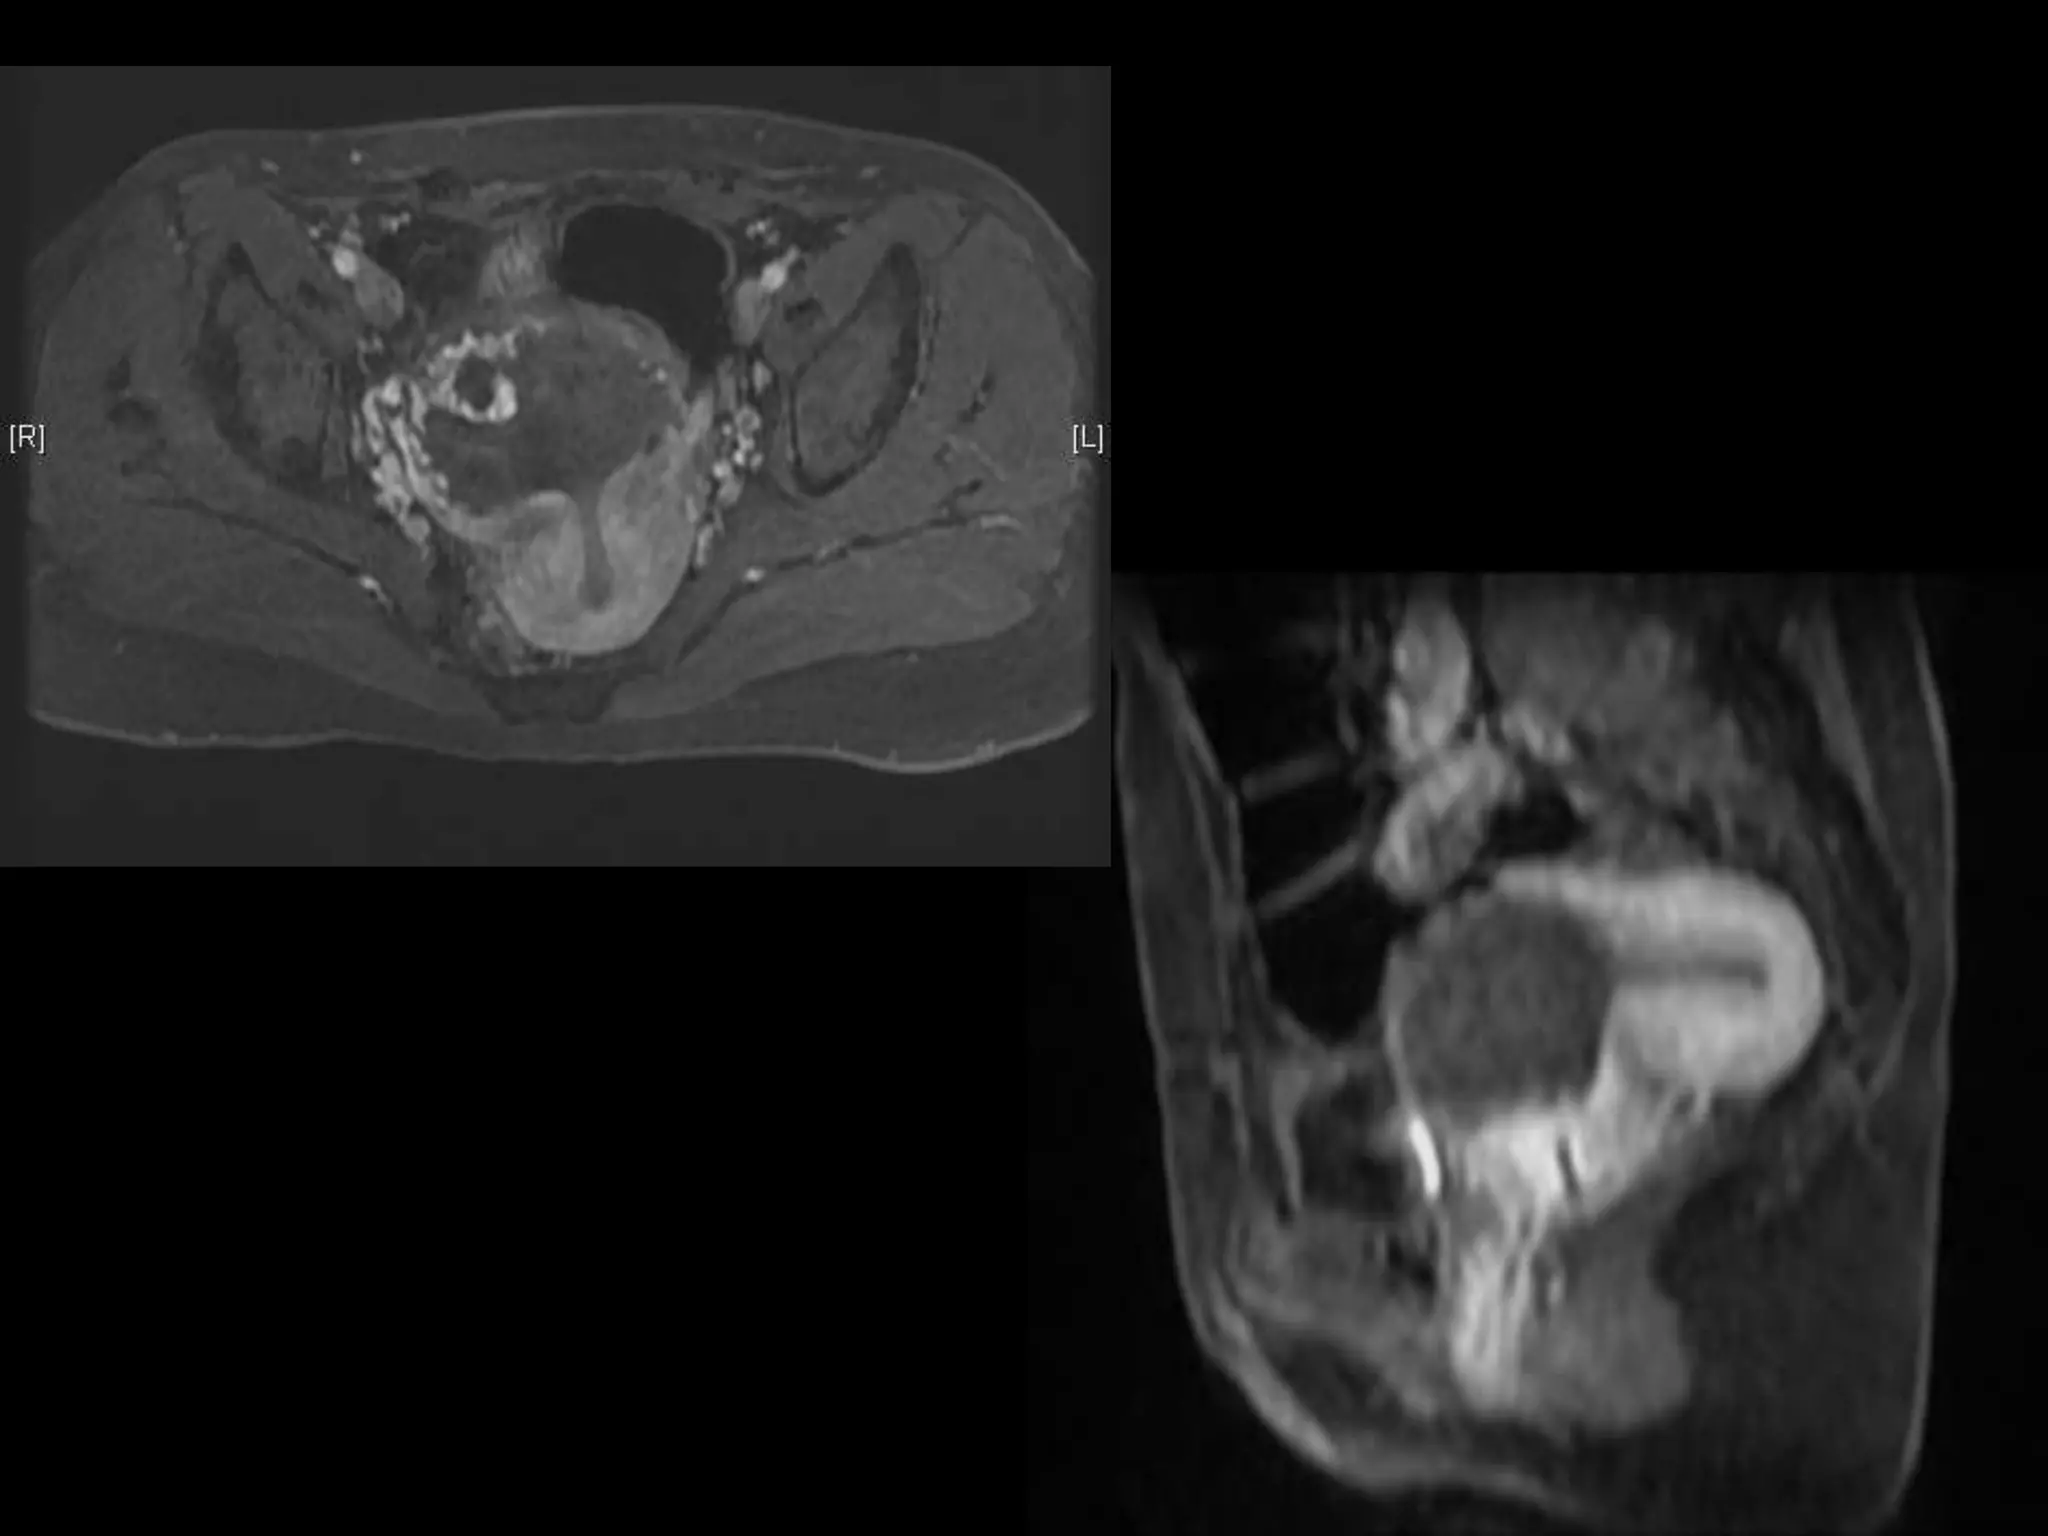

Dr. Anne Silas

HISTORY

โ€ข 40 yo female 8.5 weeks pregant

โ€ข S/P D&C for pregnancy implanted at site of

c-section scar

โ€ข 6 weeks post D&C patient presents with

heavy persistent bleeding

โ€ข For Pelvic US

โ€ข HCG = 451 mIU/mL

D&C complicated by Perforation,

AVM w RPOC at Site of Perforation

โ€ข AVM โ€“ Acquired or Congenital

โ€ข Acquired

โ€“ Traumatic โ€“ D&C, TAB, uterine surgery

โ€“ Less common: Endometrial / Cervical CA, GTD

โ€“ Clue on US: numerous tortuous vessels, high velocities

โ€ข Tx:

โ€“ transcatheter arterial embolization

โ€ข Potential to preserve fertility

โ€“ UA ligation, hysterectomy

Angio after MRI

POST PROCEDURE

S/P embolization of right UA and left UA due to

cross collateralization

1 month follow up

HCG < 5 mIU/mL

No flow in area โ€“ smaller in size

Felt residual hematoma

Will continue US follow up

HISTORY โ€ข 40 yofemale 8.5 weeks pregant โ€ข S/P D&C for pregnancy implanted at site of c-section scar

• 42.

โ€ข 6 weekspost D&C patient presents with heavy persistent bleeding โ€ข For Pelvic US โ€ข HCG = 451 mIU/mL

D&C complicated byPerforation, AVM w RPOC at Site of Perforation โ€ข AVM โ€“ Acquired or Congenital โ€ข Acquired โ€“ Traumatic โ€“ D&C, TAB, uterine surgery โ€“ Less common: Endometrial / Cervical CA, GTD โ€“ Clue on US: numerous tortuous vessels, high velocities โ€ข Tx: โ€“ transcatheter arterial embolization โ€ข Potential to preserve fertility โ€“ UA ligation, hysterectomy

POST PROCEDURE S/P embolizationof right UA and left UA due to cross collateralization

1 month followup HCG < 5 mIU/mL No flow in area โ€“ smaller in size Felt residual hematoma Will continue US follow up